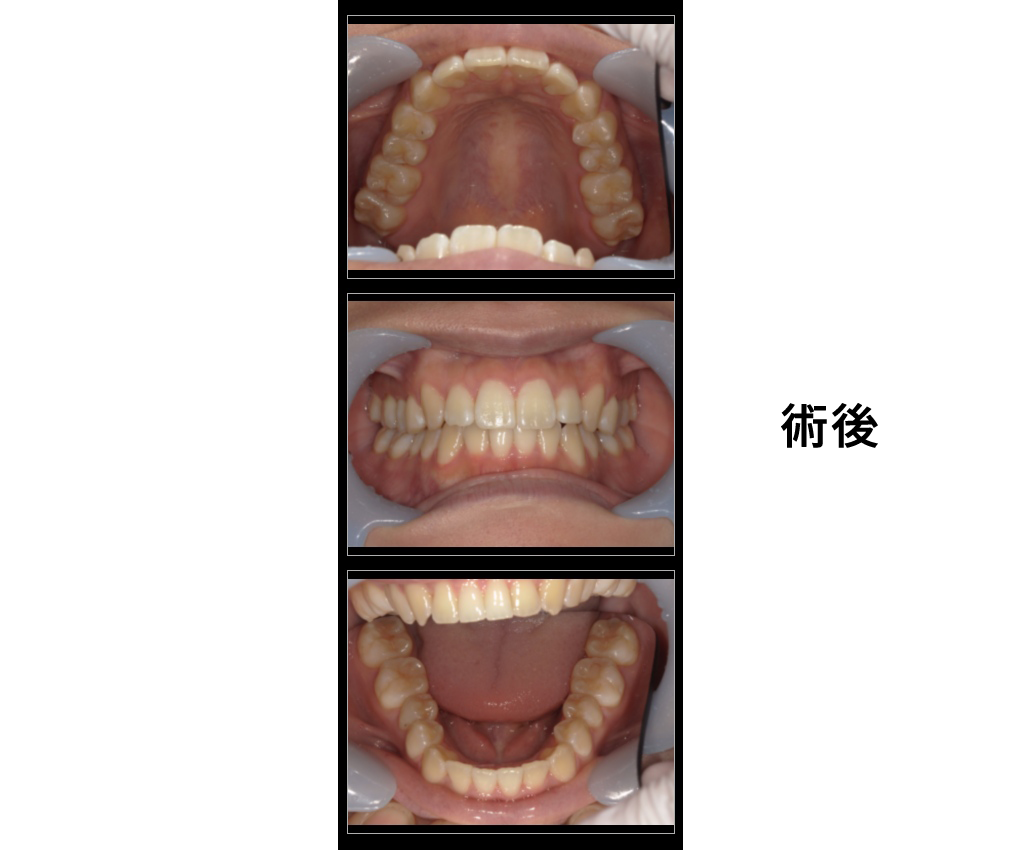

女性・25歳

治療内容:前歯の被蓋をなおしたい

→インビザラインGOにて矯正治療

金額:診断22000円、矯正440000円

来院理由:前歯の歯並びを治したい

施術の副作用(リスク):

痛みや違和感を感じることがあります。歯が一時的に動揺することがあります。

咬みにくさをかんじることがあります。